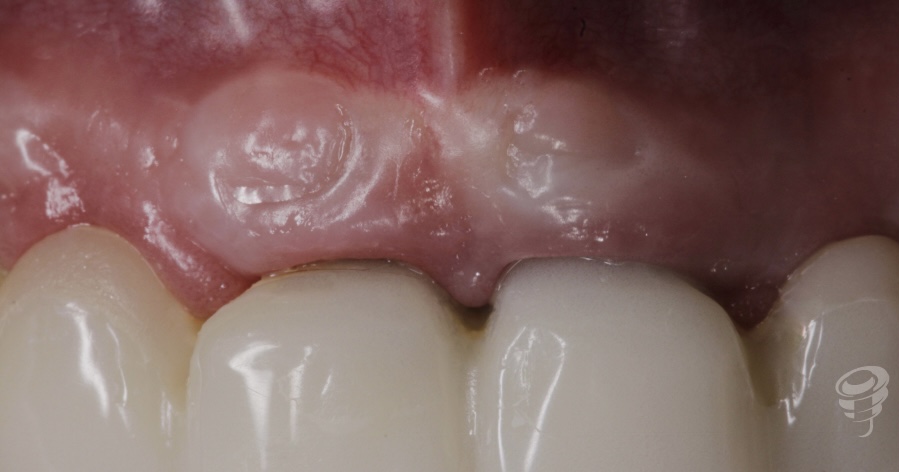

1 semana de post operatorio. La papila central se mantiene estable en su posición.

Figura 8